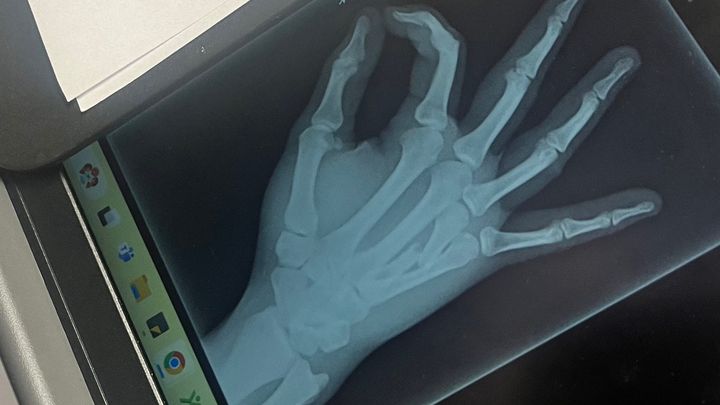

Hi everyone, I’m reaching out to ask for your help. My son, Bryson, recently broke his hand, specifically the third metacarpal, and he urgently needs surgery to fix it. The operation is scheduled for this Wednesday, but here's the challenge: since we're paying in cash, we need to cover the costs in advance by tomorrow.